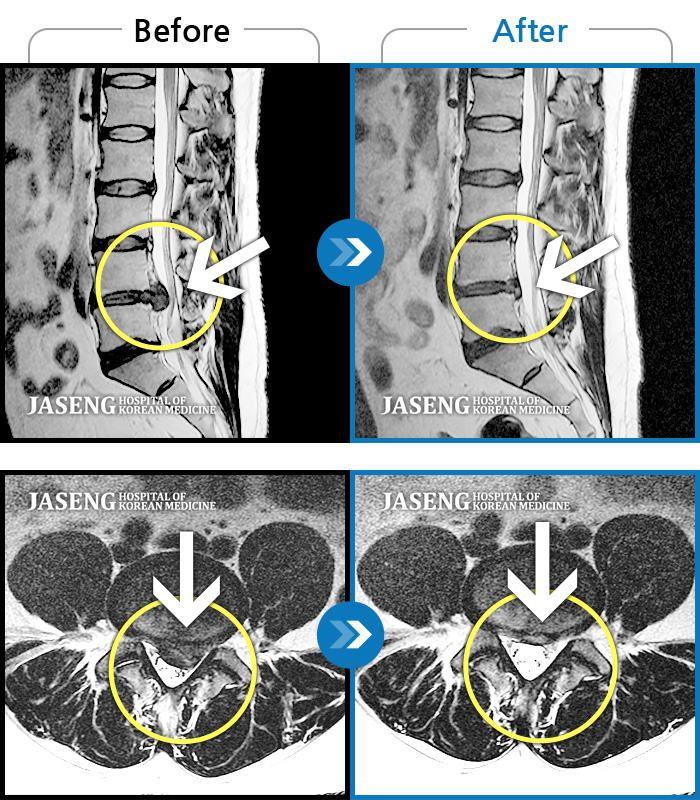

Before

After

환자에게 사전 동의를 받아 동일 조건에서 촬영되었습니다.

개인에 따라 치료 후 부작용이 발생할 수 있으니 의료진과 상담 후 치료를 진행하시기 바랍니다.

허리 우측 골반 통증, 우측 다리 저리고 엄지발가락 마비 증상

허리의 통증과 우측 다리로 방사되는 통증